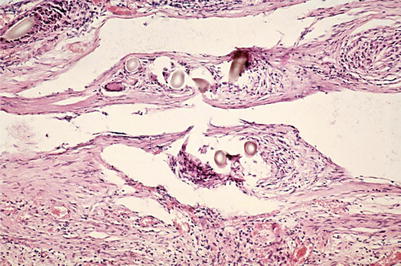

Between day 14 and 60 random investigations by electron microscopy were performed.

In normal abdominal thoracic ducts, the endothelium was smooth. The endothelial cells were closely connected, sometimes showing microvilli. Collagen fibers type I showed an exact arrangement in alternate directions. In between collagen fibers of type III were seen. Within the deeper layers of the lymphatic wall, fibrocytes, some capillaries, and single fat cells were seen.

In contrast, 14 days after allogeneic transplantation, no continuous endothelial covering could be detected. Instead, the inner surface was covered by a fibrous network. The formerly structured arrangement of collagen fibers was destructed. Collagen fibers type I and II were thus present on the inner surface.

Within blood-containing vessels, the collagen fibers type III would increase the risk of thrombosis. In lymphatic vessels, however, no significant thrombosis was seen. The reason for this might be that the potential of coagulation is reduced in lymphatic fluid to about one-third, and therefore no thrombosis was detected (Yoffey and Courtice 1970).

During weeks 3 and 4, a neointima started from the adjoining intact duct to cover the whole inner surface of the transplants. Blood capillaries grow in the vessel wall toward the neointima.

Between days 40 and 60, within the wall caverns appeared, together with a massive infiltration of activated lymphocytes, plasma cells, macrophages, and erythrocytes. The wall however remained stable because of the new endothelium and the subendothelial tissue containing a continuous basal membrane, structured collagen fibers type I, and differentiated muscle cells (Figs. 2.14, 2.15, and 2.16).

Fig. 2.14

Allogeneic abdominal thoracic duct graft of rat. 40 days after grafting (ultrathin section, 1000-fold magnification) (E endothelial cell, LU lumen, cF collagen fibers)